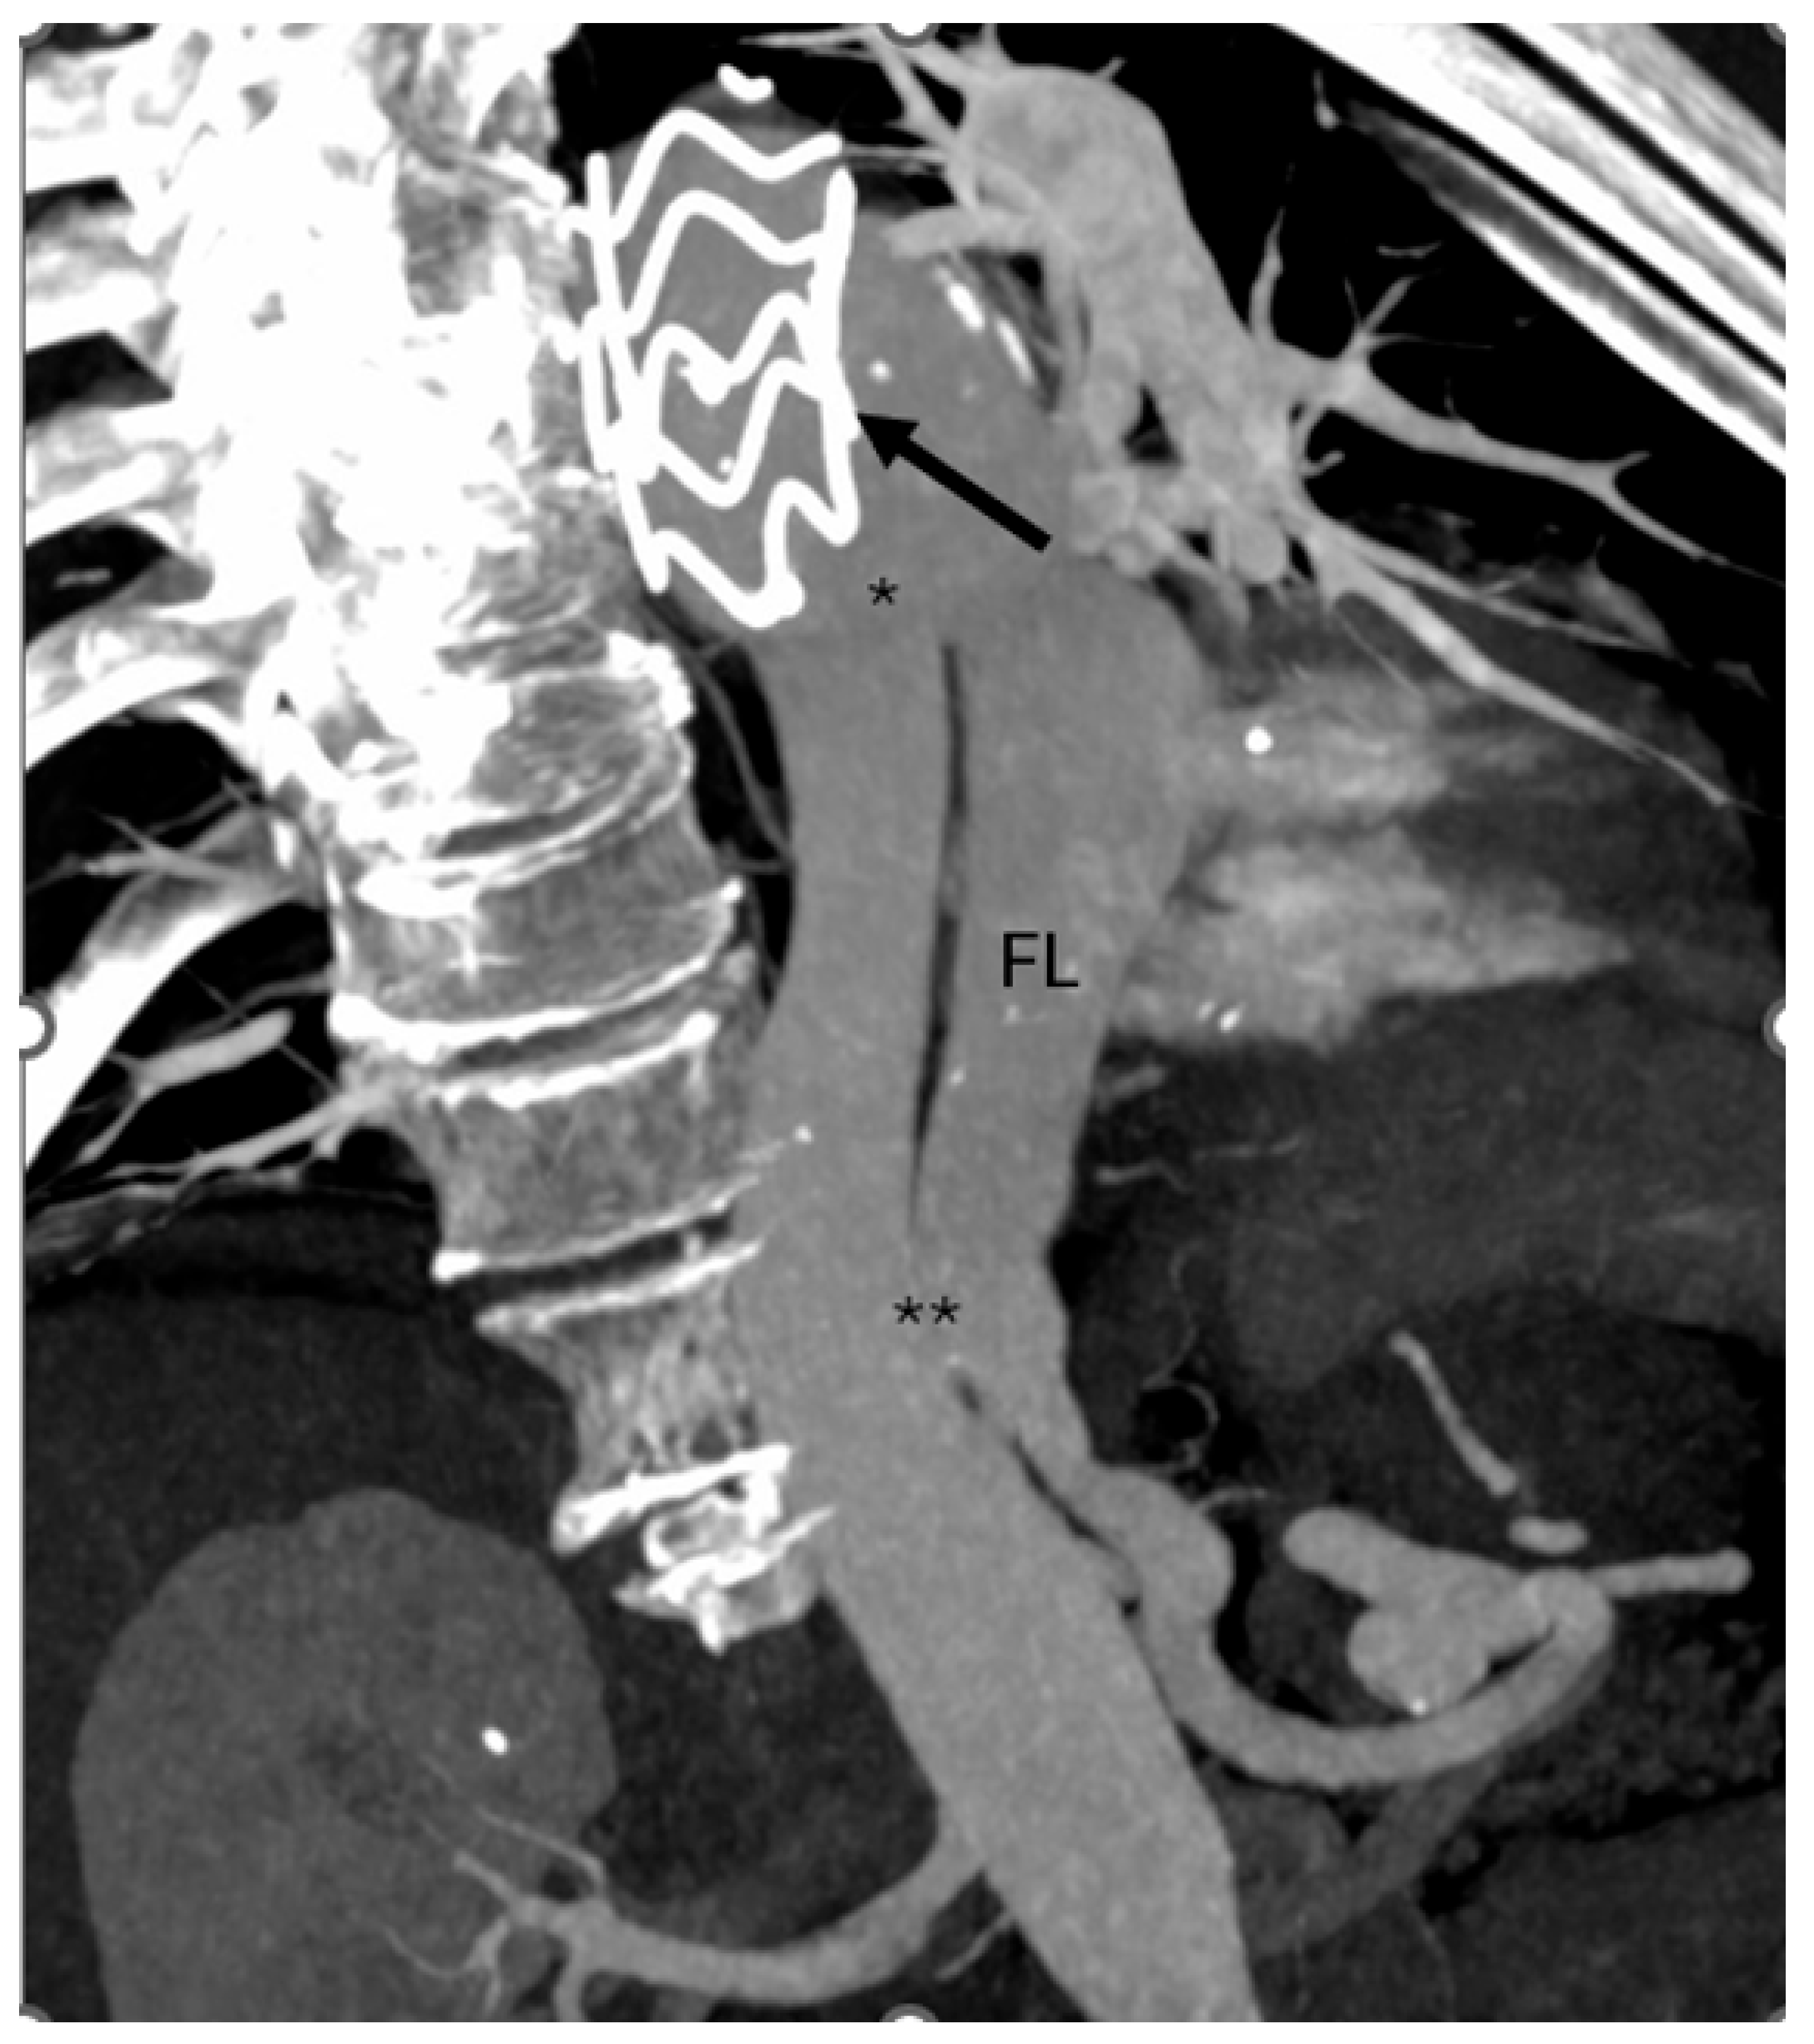

Follow-up computed tomography angiography (CTA) carried out in June 2025 revealed recanalization of the FL, extending from the distal aortic arch (zone 3) to the level of the superior mesenteric artery (zones 6–7). The descending thoracic aorta (DTA) demonstrated aneurysmal degeneration, with a maximum diameter of 58.5 mm (Figure 1).

Figure 1.

Computed tomography angiography (CTA) showing prior TEVAR (arrow) with recanalization of the false lumen (FL) through a proximal tear (*) near the stent graft and a distal tear (**) in zones 6–7.